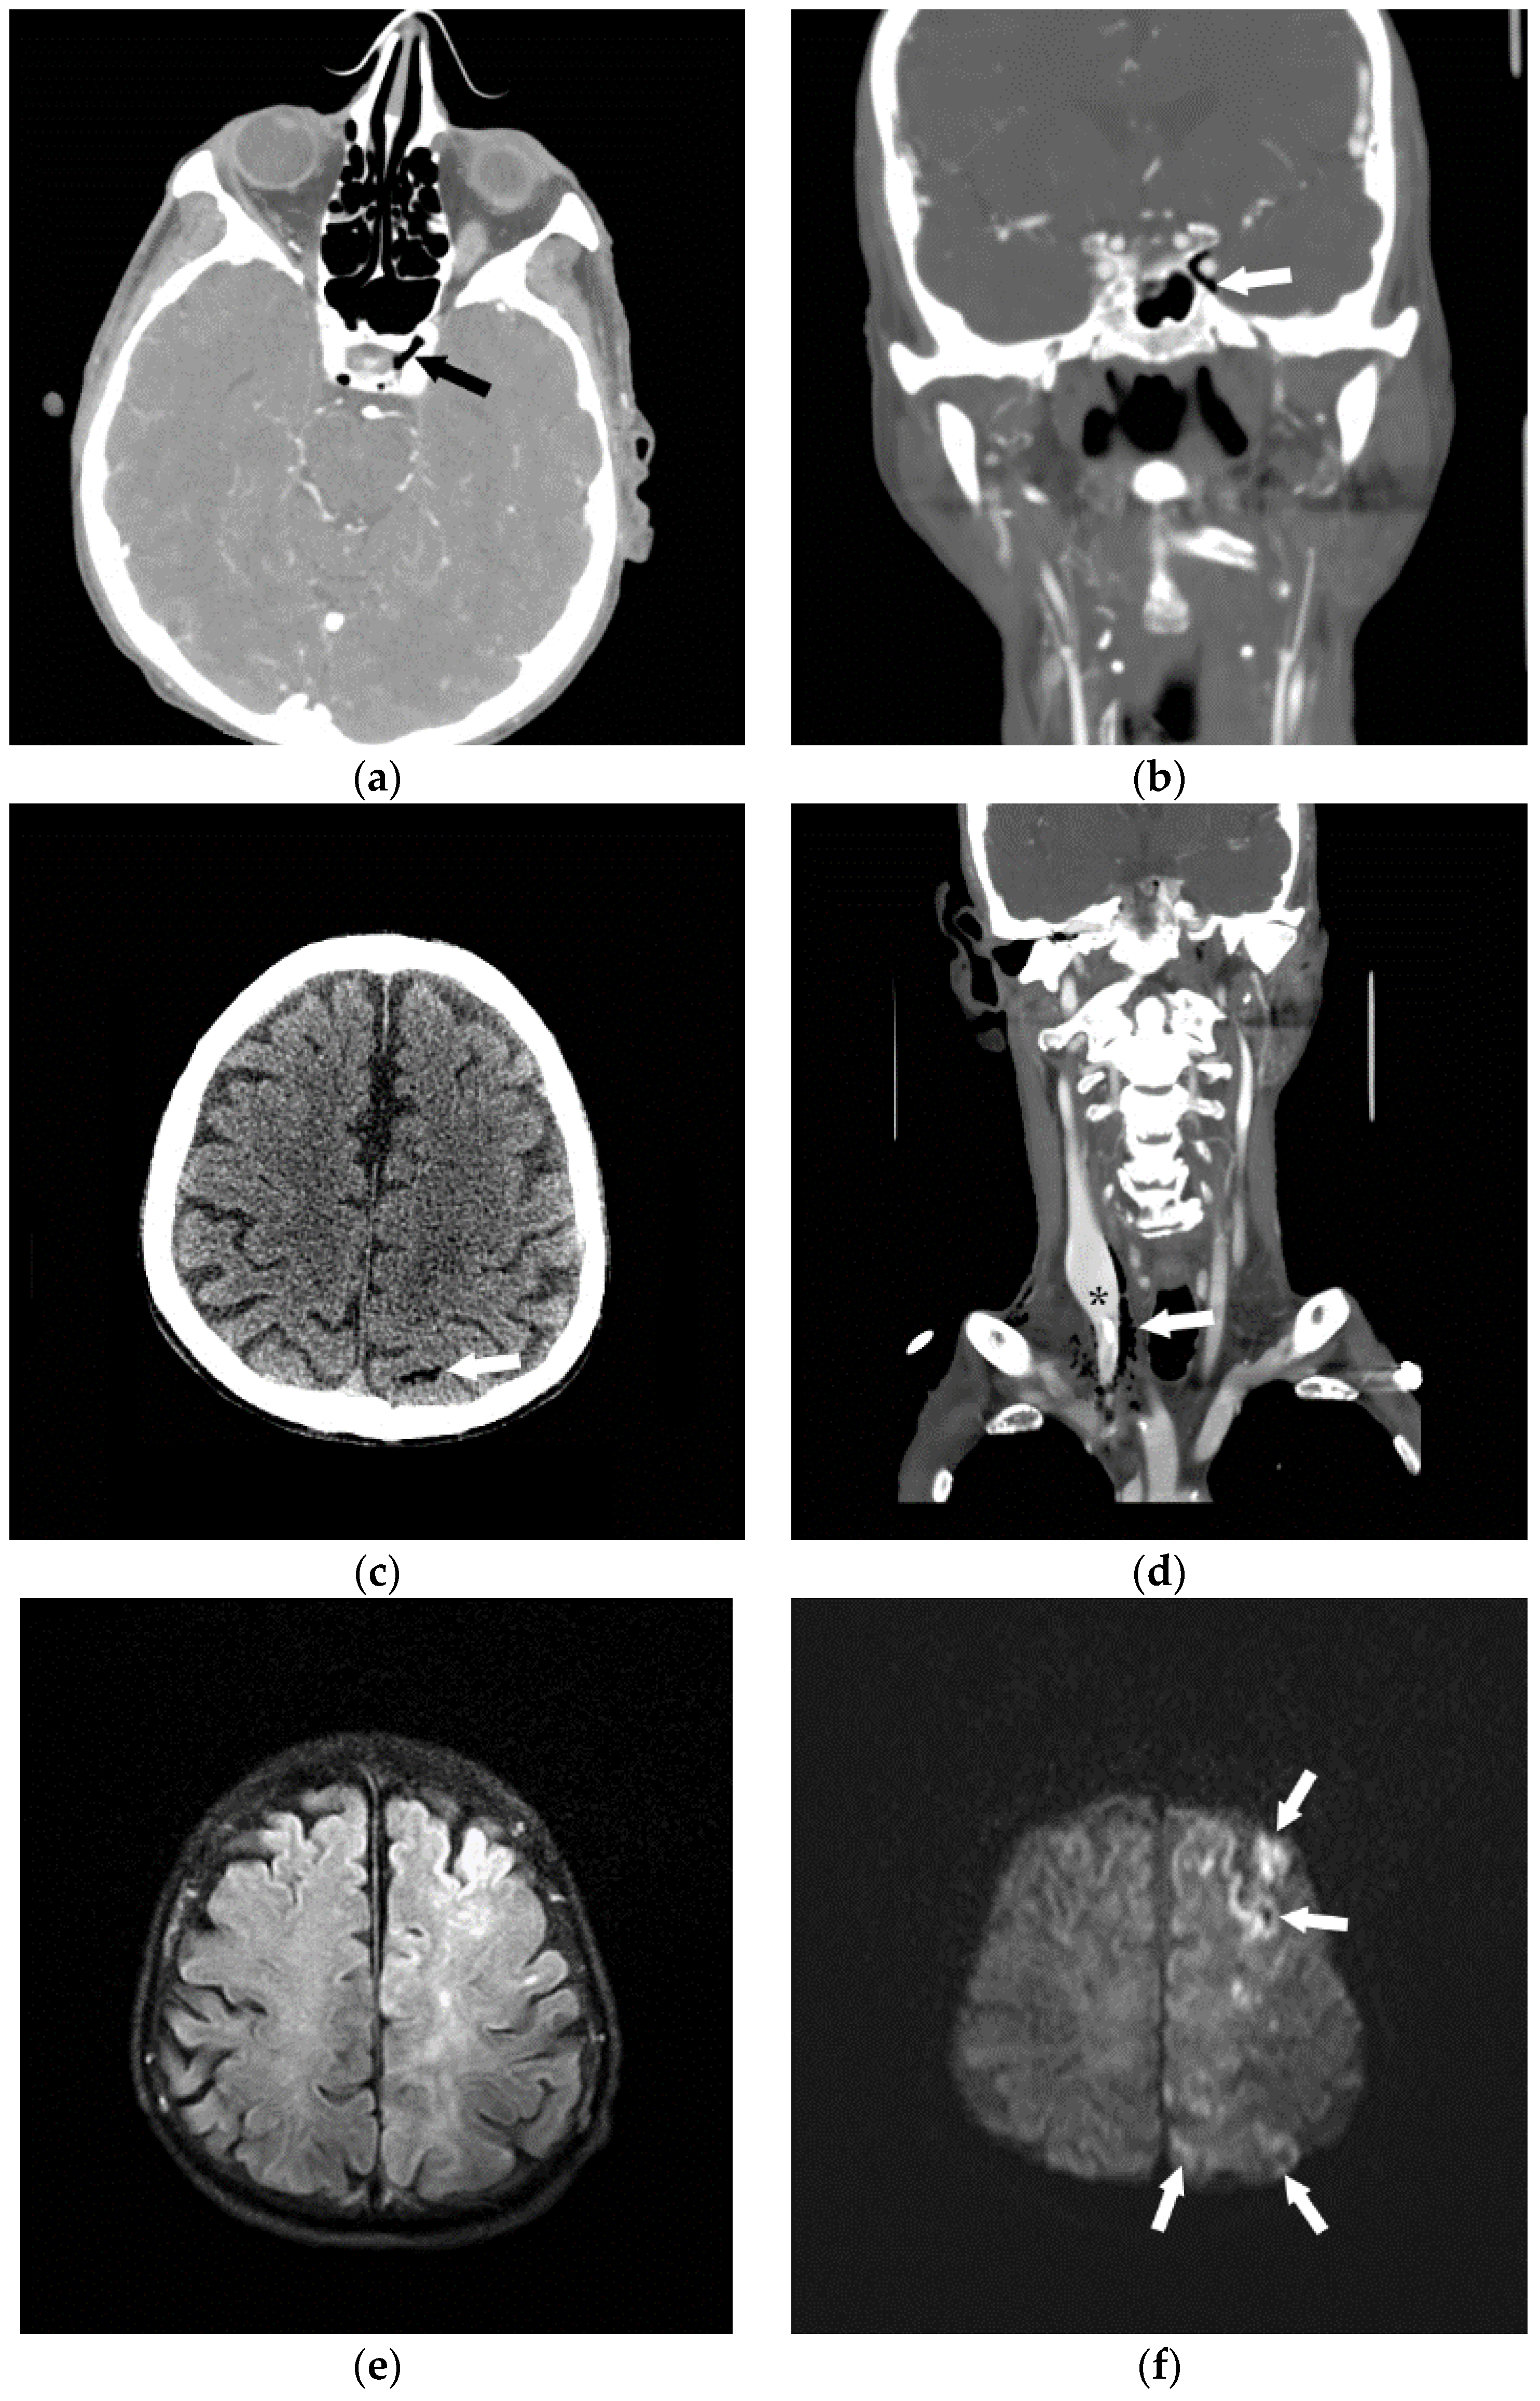

2. Etiology of Air Embolism

3. Clinical Presentation Following Air Embolus

5. Air Embolism Management

5.1. Initial Management Techniques

5.2. Advanced Management

6. Hyperbaric Oxygen Therapy